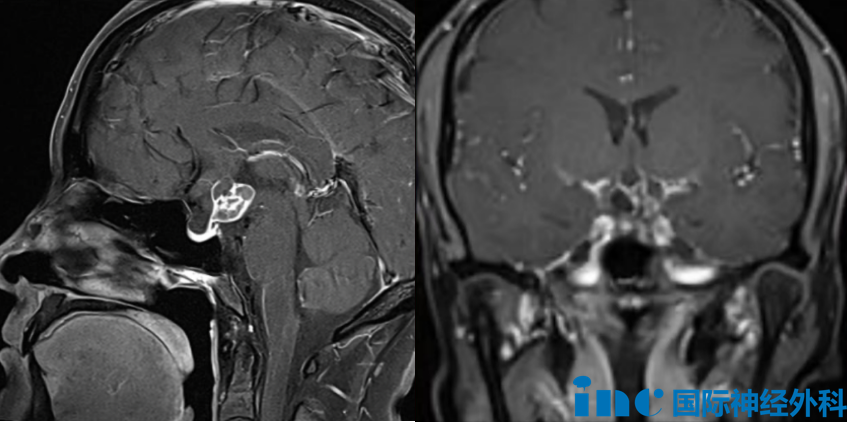

已经年过六十的周女士,确诊为枕骨大孔区脑膜瘤。影像检查结果显示,这个肿瘤已经对大脑与脊髓的连接通道——脑干下部和上段颈髓产生了显著压迫。这个区域堪称大脑与脊髓传输的“咽喉要道”,其中密布着控制呼吸功能、心跳节律及肢体活动的关键神经结构与重要血管。手术操作既需要医生在颅底区域、脑干组织、脊髓结构及血管外科方面具备丰富的手术经验,也要求主刀医生对该区域的解剖结构拥有深刻的理解能力,任何微小的操作误差都可能导致瘫痪、呼吸功能衰竭等不可逆的严重后果。

枕骨大孔区,从右背外侧和下角观察颅骨(a)和右背外侧颅骨区图示(b)